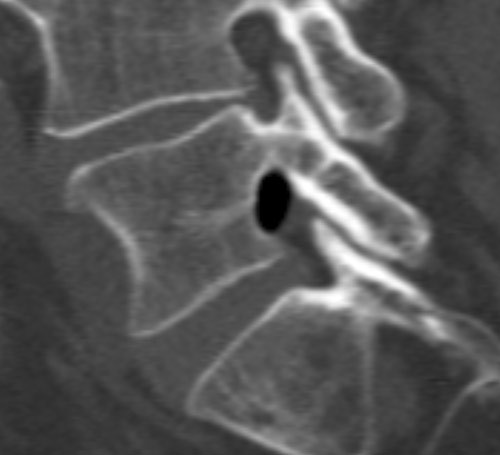

En mann i 60-årene ble innlagt med to dagers sykehistorie med venstresidig isjialgi og pareseutvikling i L5-innervert muskulatur. MR viste en oppfylling i venstre laterale recess i nivå L4/L5 med dorsal dislokasjon av venstre L5-rot. Oppfyllingen hadde uvanlig lavt MR-signal som ga mistanke om forkalkninger eller luft. Supplerende CT viste en velavgrenset luftansamling i samme område (bildene).

Klinisk forverring førte til kirurgisk eksplorasjon av L5-roten. Ventralt for denne så man en luftmengde innkapslet i epiduralt bløtvev, incisjon ble foretatt og luften sluppet fri. Etter dette var L5-roten mykere palpatorisk og hadde fritt forløp. Pasienten opplevde betydelig bedring postoperativt.